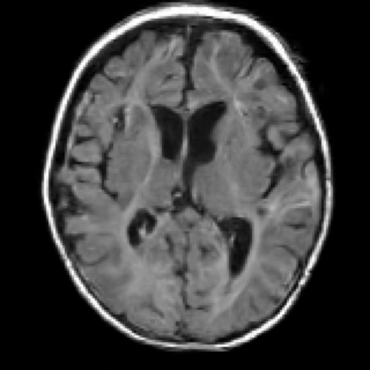

A sample of uLF, our MRIQT, and the HF for a selected case